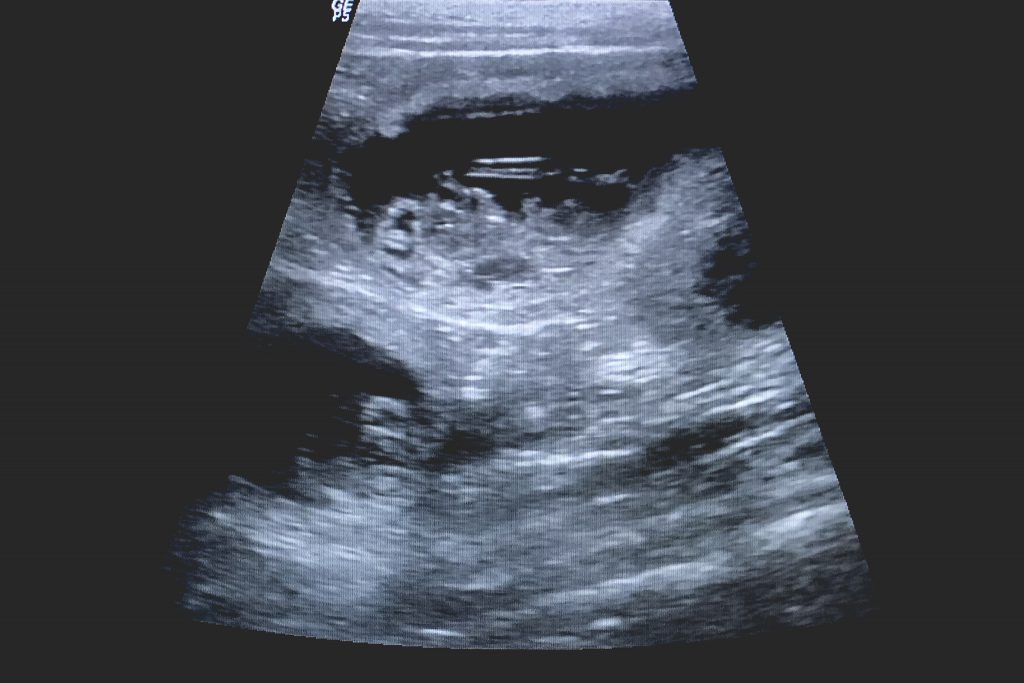

Wenn aus Träumen schlagende Herzen und aus Wünschen winzige Pfoten werden, dann kann das nur eins sein: ein Wunder.